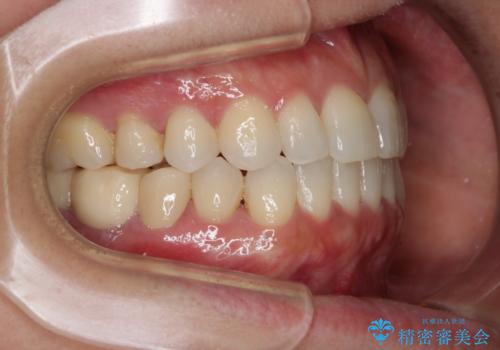

早い安いきれい!インビザラインライトで前歯のでこぼこ、反対咬合をなおす

- 前歯のがたつきと反対咬合を主訴に来院されました。

インビザライン・クリンチェック(歯のシミュレーション)を行い、

インビザラインライトで治せる範囲であることを確認し治療を開始することになりました。

今回はクリンチェックを作成したのちに、枚数が少なくても可能であることが判明したためインビザラインライトでの治療を行いました。

最初はインビザラインモデレートパッケージの予定で契約をされていたので、金額も10万円以上安くなり仕上がりも満足頂きました。